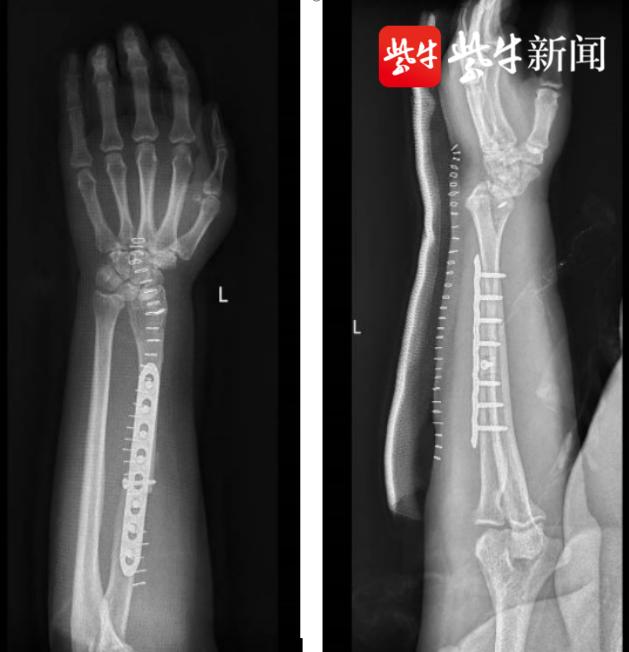

术后腕关节已经顺利重建

经过术前精确测量,该患者需要切除包括桡骨远端关节面在内的瘤段大于7cm,如此长度的长骨缺损,势必会影响今后左臂的功能。考虑到鲁女士比较年轻,马益民主任医师团队决定从患者实际需求出发,在汇报骨科主任殷国勇教授并与患者及患者家属反复交流沟通后,制定了个体化的手术方案,选择骨科难度较高的术式之一——桡骨远段肿瘤瘤段切除+同侧自体带血管蒂腓骨移植重建术。

马益民主任医师表示,该方案比常规方案难度更高,耗费精力和时间更多,因为兼顾了“切”和“种”:“切”采用阶梯型截骨重建,保证了肿瘤段的完整切除,“种”则是同侧自体带血管蒂腓骨移植,可以让移植过来的腓骨在移植区保持血供,继续“生长发育”。这样不仅前臂和腕部形态能恢复如初,而且更有利于患者前臂和腕关节功能和力量的恢复。

近日,经过马益民主任医师团队7个小时的攻坚,手术顺利完成。鲁女士术后恢复良好,左手腕关节在经过康复和锻炼后,也逐渐恢复了往日的功能。